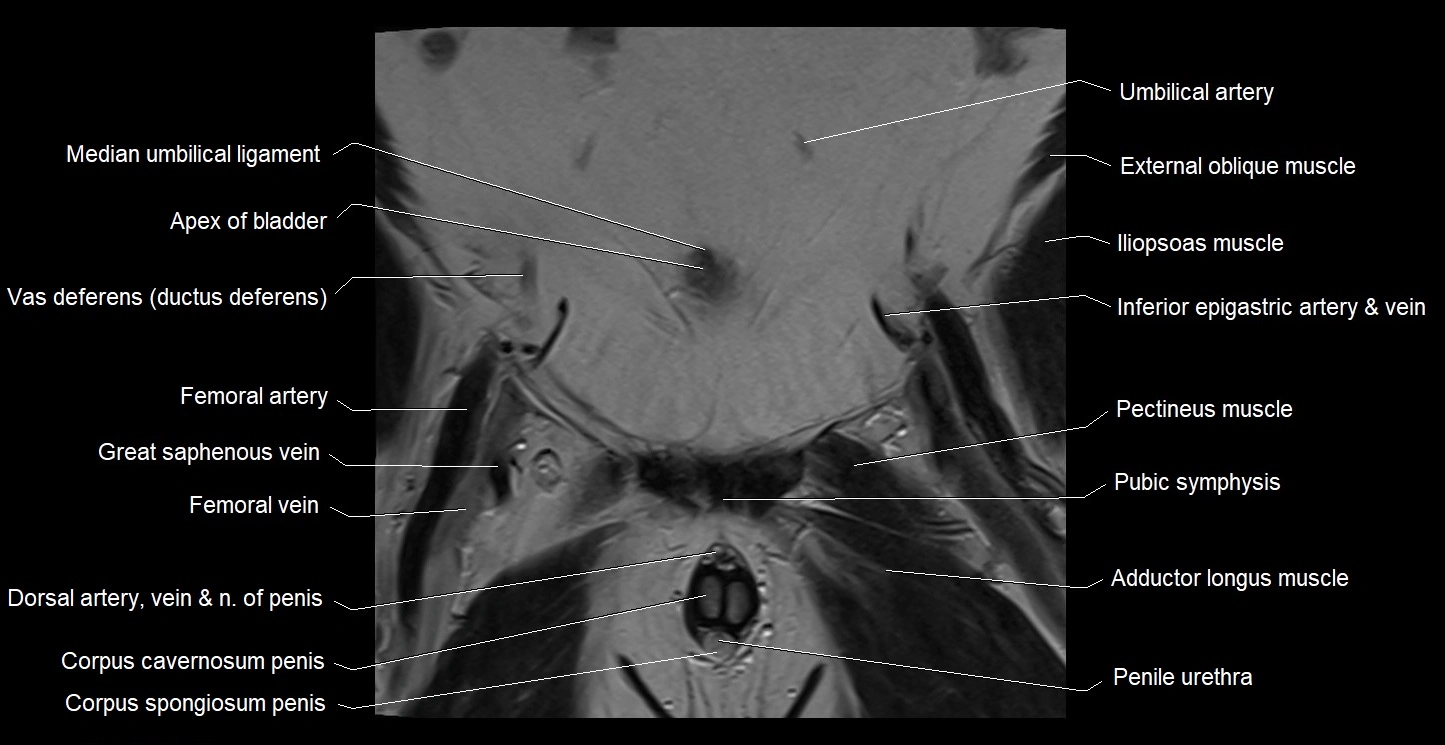

- Apex of urinary bladder

- Femoral artery

- Femoral vein

- Gracilis muscle

- Iliopsoas muscle

- Median umbilical ligament

- Mediastinum testis

- Pectineus muscle

- Penile urethra

- Pubic symphysis

- Umbilical artery

- Vas deferens